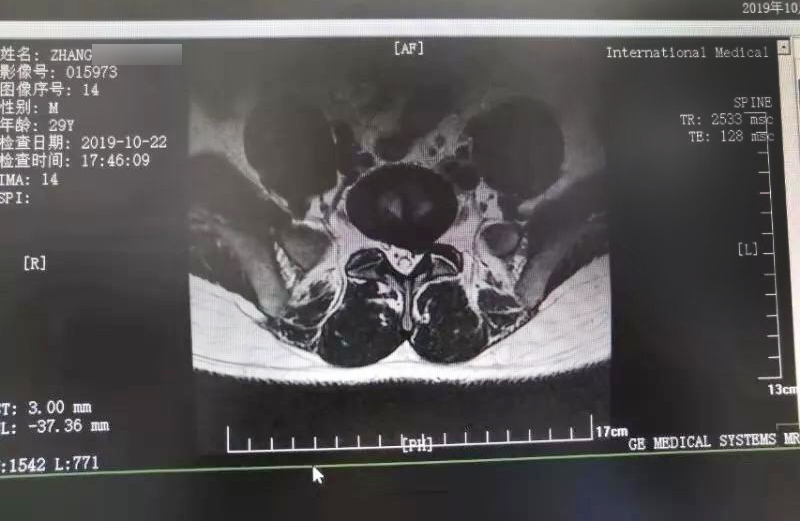

三秦網(wǎng)報道—西安國際醫(yī)學中心骨科醫(yī)院成功完成首例椎間孔鏡手術

三秦網(wǎng)報道—西安國際醫(yī)學中心骨科醫(yī)院成功完成首例椎間孔鏡手術。點擊閱讀。